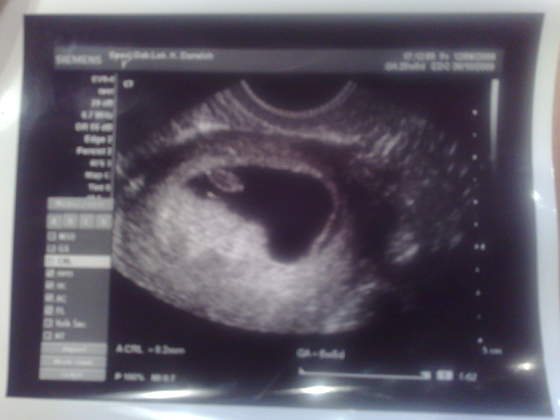

no wlasnie nie znam sie na tym dlatego sie zastnawiam jak to naparwde powinno wygladacja mialam w 6tyg i 5 dni zarodek 8,3 mm i serduszko 140uderzen na min. a pecherzyk nie wiem ile mial ale byl duuuuzy... moze nzajde fotke.